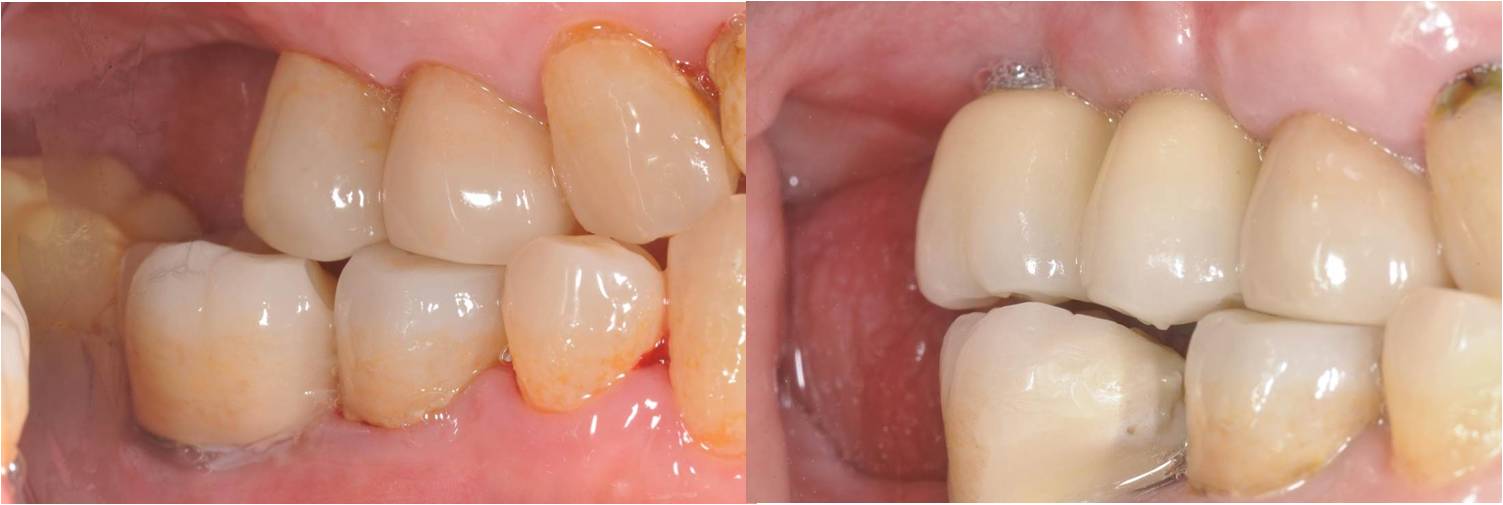

術前、術後比較

透過適當的植牙手術與膺復處置,患者可以恢復正常的咀嚼與美觀功能,在後牙區如果採螺絲固定型假牙,則回診時,醫生只要將螺絲鬆開清潔假牙,對於後續後續清潔與維護有莫大的幫助。